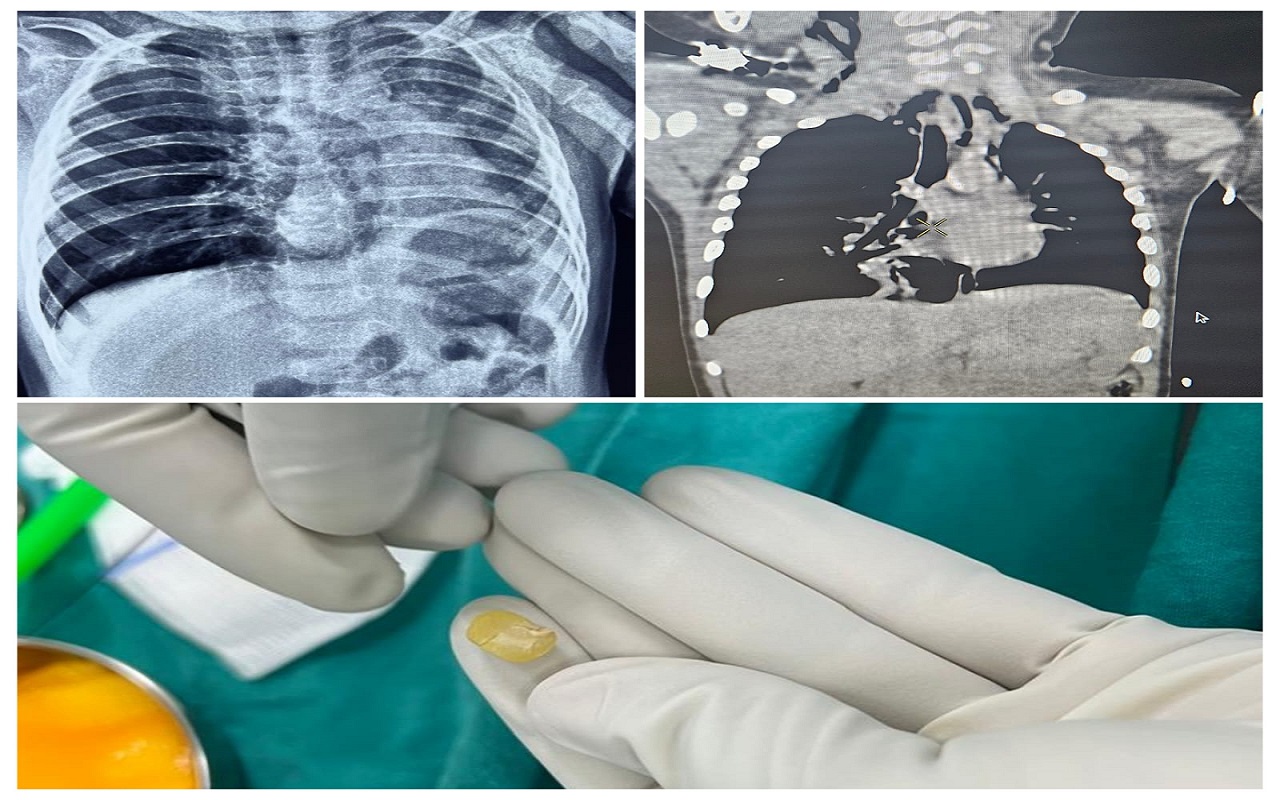

ಮಂಗಳೂರು: ಶ್ವಾಸನಾಳದಲ್ಲಿ ಕಡಲೇ ಬೀಜ ಸಿಲುಕಿ ತೀವ್ರ ಮಟ್ಟದ ಉಸಿರಾಟದ ಸಮಸ್ಯೆಗೆ ಒಳಗಾಗಿದ್ದ 10 ತಿಂಗಳ ಮಗುವನ್ನು ರಕ್ಷಿಸುವಲ್ಲಿ ಮಂಗಳೂರಿನ ಕೆಎಂಸಿ ಆಸ್ಪತ್ರೆಯ ವೈದ್ಯರ ತಂಡ ಯಶಸ್ವಿಯಾಗಿದೆ.

ಪೋಷಕರು ಸಾಮಾನ್ಯ ಶೀತ ಸಮಸ್ಯೆ ಎಂದು ತಿಳಿದು ಪುತ್ತೂರಿನ ಡಾ .ಶ್ರೀಕಾಂತ್‌ ರಾವ್‌ ಬಳಿ ತಪಾಸಣೆಗೆ ಕರೆದೊಯ್ದಿದ್ದಾರೆ. ಅಲ್ಲಿ ವೈದ್ಯರು ಎಕ್ಸ್‌ ರೇ ತಪಾಸಣೆಯಲ್ಲಿ ಮಗುವಿನ ಶ್ವಾಸನಾಳದಲ್ಲಿ ಯಾವುದೋ ವಸ್ತು ಸಿಲುಕಿರುವ ಶಂಕೆ ವ್ಯಕ್ತಪಡಿಸಿದ್ದಾರೆ. ತಕ್ಷಣ ಮಗು ವನ್ನು ಕೆಎಂಸಿ ಆಸ್ಪತ್ರೆಗೆ ಕರೆತರಲಾಗಿದ್ದು ಡಾ. ಸ್ವಾತಿ ರಾವ್‌ ತಪಾಸಣೆಯಲ್ಲಿ ಮಗುವಿನ ಸ್ಥಿತಿ ಗಂಭೀರವಾಗಿರುವುದನ್ನು ಪತ್ತೆಹಚ್ಚಿದ್ದಾರೆ. ಅದಾಗಲೇ ಮಗುವಿನ ಆಕ್ಸಿಜನ್‌ ಸ್ಯಾಚುರೇಶನ್‌ 88 ಕ್ಕೆ ಕುಸಿದಿತ್ತು. ಸಿಟಿ ಸ್ಕ್ಯಾನ್‌ನಲ್ಲಿ ಮಗುವಿನ ಬಲ ಶ್ವಾಸನಾಳ ದಲ್ಲಿ ಚಿಕ್ಕದೊಂದು ವಸ್ತು ಸಿಲುಕಿರುವುದು ಪತ್ತೆಯಾಗಿದೆ.

ಹೇಗಿತ್ತು ಚಿಕಿತ್ಸೆ

ಶ್ವಾಸನಾಳದಲ್ಲಿ ಕಡಲೇಬೀಜದ ತುಣುಕು ಸಿಲುಕಿರುವ ಕಾರಣ ಬಲ ಶ್ವಾಸಕೋಶದಲ್ಲಿ ಉಬ್ಬರ ಮತ್ತು ಎಡ ಶ್ವಾಸಕೋಶ ಮತ್ತು ಹೃದಯದ ಸಂಕೋಚನ ಕಂಡುಬಂದಿದೆ. ಮಗುವನ್ನು ತಕ್ಷಣ ಶಸ್ತ್ರಚಿಕಿತ್ಸಾ ಕೊಠಡಿಗೆ ಕರೆದೊಯ್ಯಲಾಗಿದ್ದು ಡಾ. ಗೌತಮ್‌ ಕುಲಮರ್ವಾ ತುರ್ತು ಬ್ರೊಂಕೊಸ್ಕೊಪಿಕ್‌ ವಿಧಾನ ಕೈಗೊಳ್ಳುವ ಮೂಲಕ ಕಡಲೆಬೀಜದ ತುಣುಕನ್ನು ಯಶಸ್ವಿಯಾಗಿ ಹೊರತೆಗೆದಿದ್ದಾರೆ. ಮಗುವು ಉಸಿರಾಟದ ಸಮಸ್ಯೆಗೆ ಒಳಗಾಗಿ 18 ಗಂಟೆ ಕಳೆದಿದ್ದ ಕಾರಣ ಶ್ವಾಸನಾಳದಲ್ಲಿ ನೀರು ತುಂಬುವ ಲಕ್ಷಣವೂ ಆರಂಭ ವಾಗಿತ್ತು.